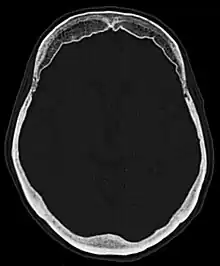

Hyperostosis frontalis interna is a common, benign thickening of the inner side of the frontal bone of the skull. It is found predominantly in women after menopause and is usually asymptomatic. Mostly frequently it is found as an incidental finding discovered during an X-ray or CT scan of the skull.

Hyperostosis frontalis at CT